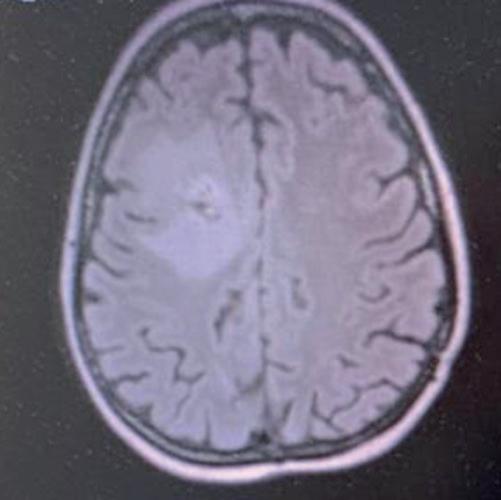

Alla RMN encefalo del 18/02/2022, in sede cerebellare sinistra si conferma la presenza di alterazione sospetta in senso ripetitivo di 15 mm, adesa alla dura madre.

Si evidenzia alterazione osteostrutturale patologica della teca cranica in sede temporo-parietale destra associata a ispessimento lineare della meninge adiacente (figura 3).

TC e RMN encefalo con mdc, febbraio 2022.

Figura